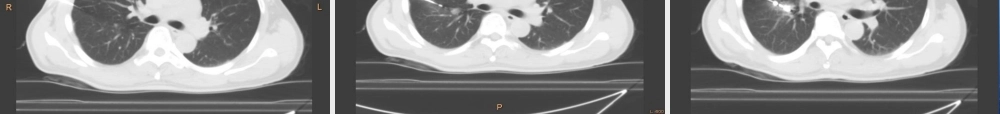

CT 引导下的穿刺技术CT 引导下的穿刺技术定义• 指在 CT 机的引导下利用穿刺针经皮穿刺进入脏器或组织,获取细胞学或组织学材料,以明确病变性质的一种特殊的检查方法。CT 引导下的穿刺技术背景• 1976 年 Haage 首次报道了 CT 引导下的经皮穿刺技术,开辟了以 CT 作为引导方法的先河。• 1985 年张雪哲首先在我国将 CT 引导技术应用于临床。• 近 30 年来随着 CT 机的升级换代、穿刺针的改进、 CT立体定向技术的建立,使得 CT 引导下的穿刺技术可用于全身各个部位病变的诊断,同时也是 CT 引导下的肿瘤微创治疗的基础。CT 引导下的穿刺技术的优势• CT 分辨率高,图像清晰(最小可见 2mm 病变)。• CT 图像不受空腔脏器及气体干扰,断层扫描图像层次分明,影像无重叠。• CT 增强图像及三维重建图像,使得病变与周围组织结构关系更加清晰,图像更加生动立体。CT 引导下热消融治疗的含义• CT 引导下的肿瘤热消融技术是指在 CT 机的引导下将消融针经皮穿刺进入肿瘤组织,利用消融针产生的能量使肿瘤组织的温度升至 60-100 度,从而使肿瘤组织产生凝固坏死的一种方法。包括 CT 引导下的射频消融术及 CT 引导下的微波消融术。CT 引导下热消融治疗的优势• 热消融技术可以使局部肿瘤组织产生高温凝固性坏死,但不影响周围组织的结构及功能,最大限度做保护了周围正常组织,是真正意义上的微创手术。术后创伤小,恢复快,同时还能提高患者的局部抵抗力。CT 引导下的微创技术的国内外发展现状• CT 机在我国县级以上医院已相当普及,加上 CT 机本身具有检查部位广泛 , 高分辨率显像的特点使 CT 影像诊断迅速兴起并广泛应用。 CT 引导下的穿刺技术就是在 CT 影像诊断的基础上发展起来的。现已广泛应用各系统占位性病变的诊断及治疗中。• CT 引导下的穿刺技术及热消融治疗发展迅速。近 30年来 CT 引导下的穿刺技术不仅用于疾病的诊断上而且应用在脓肿的抽吸、囊肿的抽吸硬化、肿瘤的粒子植入治疗、肿瘤的消融治疗、椎间盘切吸术、神经阻滞、骨水泥成形等多种治疗方法上。 CT 引导下的微创治疗具有创伤小、恢复快、见效快、价格低廉的特点,易被广大患者接受。应用范围• 胸部穿刺活检• 纵膈肿瘤及淋巴结的病变诊断• 乳腺的穿刺活检• 腹部穿刺活检(肝脏、肾脏、胰腺、及腹部淋巴结等)• 盆腔的穿刺活检• 肌肉骨骼的穿刺活检胸部穿刺活检技术适应症• 肺部肿块的诊断...